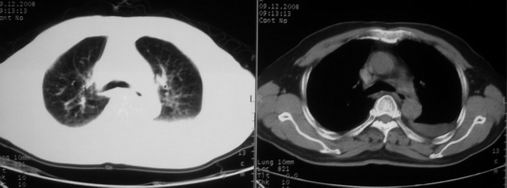

抗炎治疗一周热退,提示为炎症,现片示病灶范围增大,边缘清楚,建议继续治疗,不除外肺脓肿

炎症性病变;左侧胸腔积液。

ct左肺下叶大片状高密度影,病变密度不均,界限不清,左侧胸腔积液,治疗后复查临床症状好转而影像学表现病变有发展,还是首先考虑感染性病变,复查时间短附合感染性病变的病理改变。